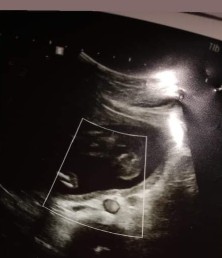

ขออนุญาตขอคำแนะนำคุณแม่ๆนะคะ คุณแม่ทานอะไรให้น้องโตขึ้นไวๆค่ะ ทางนี้อิแม่รู้สึกกังวลใจ เพราะดูในรูปอัลตร้าซาวด์รู้สึกเขาตัวเล็กมากหมออยากให้เราเพิ่มน้ำหนัก แต่น้ำหนักของลูกปกติตามเกณฑ์ดีค่ะ เป็นคนมีพุง ท้องเลยยังไม่ออกเหมือนกับคนท้องค่ะ มันดูไม่ชัดเลยว่ากำลังท้อง 5 เดือน นน.ลูก 364กรัม และมันมีอะไรบังตรงที่พุงน้องด้วยคะ มันคืออะไรค่ะ หมอบอกดูยากมาก ไขมันบังน้องหรือป่าวคะ คุณแม่รู้สึกกังวลใจมากๆค่ะ ขอคำแนะนำคุณแม่หน่อยนะคะ #ขอบคุณล่วงหน้านะคะ #ขอคำแนะนำหน่อยค่ะ #ขอบคุณสำหรับคำตอบค่ะ #ท้องแรกคะ

กำลังตั้งครรภ์